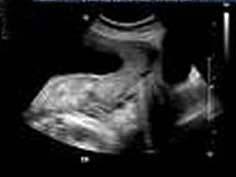

图中的胎盘为 ( )A、低置胎盘B、以上都不对C、部分性前置胎盘D、边缘性前置胎盘E、完全性前置胎盘

问题 图中的胎盘为 ( )

选项 A、低置胎盘 B、以上都不对 C、部分性前置胎盘 D、边缘性前置胎盘 E、完全性前置胎盘

答案 E